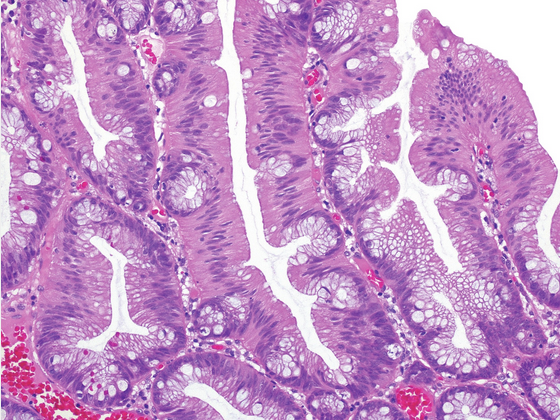

solitary rectal ulcer syndrome/mucosal prolapse.

Fibromuscular hyperplasia/obliteration of lamina propria

Architectural distortion of colonic mucosa/epithelium

Hyperplastic/villiform, regenerative surface with mucin loss

Inflammation, erosion, ulceration, pseudomembranes

Capillary proliferation with dilation below surface

Dense submucosal fibrosis with cysts often present

High-power magnification of an H&E-stained section shows characteristic hyperplastic, villiform surface epithelium ; disorganized smooth muscle fibers in the lamina propria ; and proliferating, congested capillaries in the superficial lamina propria.